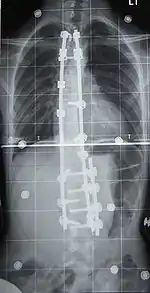

![]() Рентгеновский снимок позвоночника пациента со сколиозом с правосторонним искривлением в поясничном отделе и левосторонним искривлением в грудном отделе позвоночника. | |

При оперативном лечении позвоночник выпрямляется до определённого угла при помощи металлических стержней, что ведёт к обездвиживанию этих отделов позвоночника. Операция при сколиозе подходит прежде всего для сильных искривлений, которые больше не могут лечиться другими методами. Оперативная фиксация может предотвратить дальнейшую прогрессию и ухудшение состояния.

Оперативный разрез при заднем доступе находится на средней линии туловища и одном из крыльев тазовой кости. Используются различные системы металлических стержней, которые крючками или шурупами (т. н. педикулярными винтами) прикрепляются к позвоночнику и затем изменяют его кривизну на больших участках. Для лучшей стабилизации всей конструкции стержни имеют поперечные соединения (мостики). Сразу после операции теряется подвижность в зафиксированных отделах позвоночника. Это способствует впоследствии сращению тел позвонков в единый костный блок желаемой геометрии. Недостаток метода состоит в том, что позвоночник на больших участках оказывается обездвижен, и общая подвижность позвоночного аппарата ограничена, что вынуждает пациента менять привычные стереотипы движений.